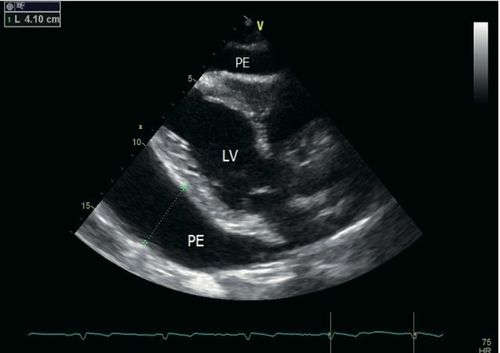

二维超声心动图:胸骨旁长轴切面显示大量环绕心包积液,舒张期为